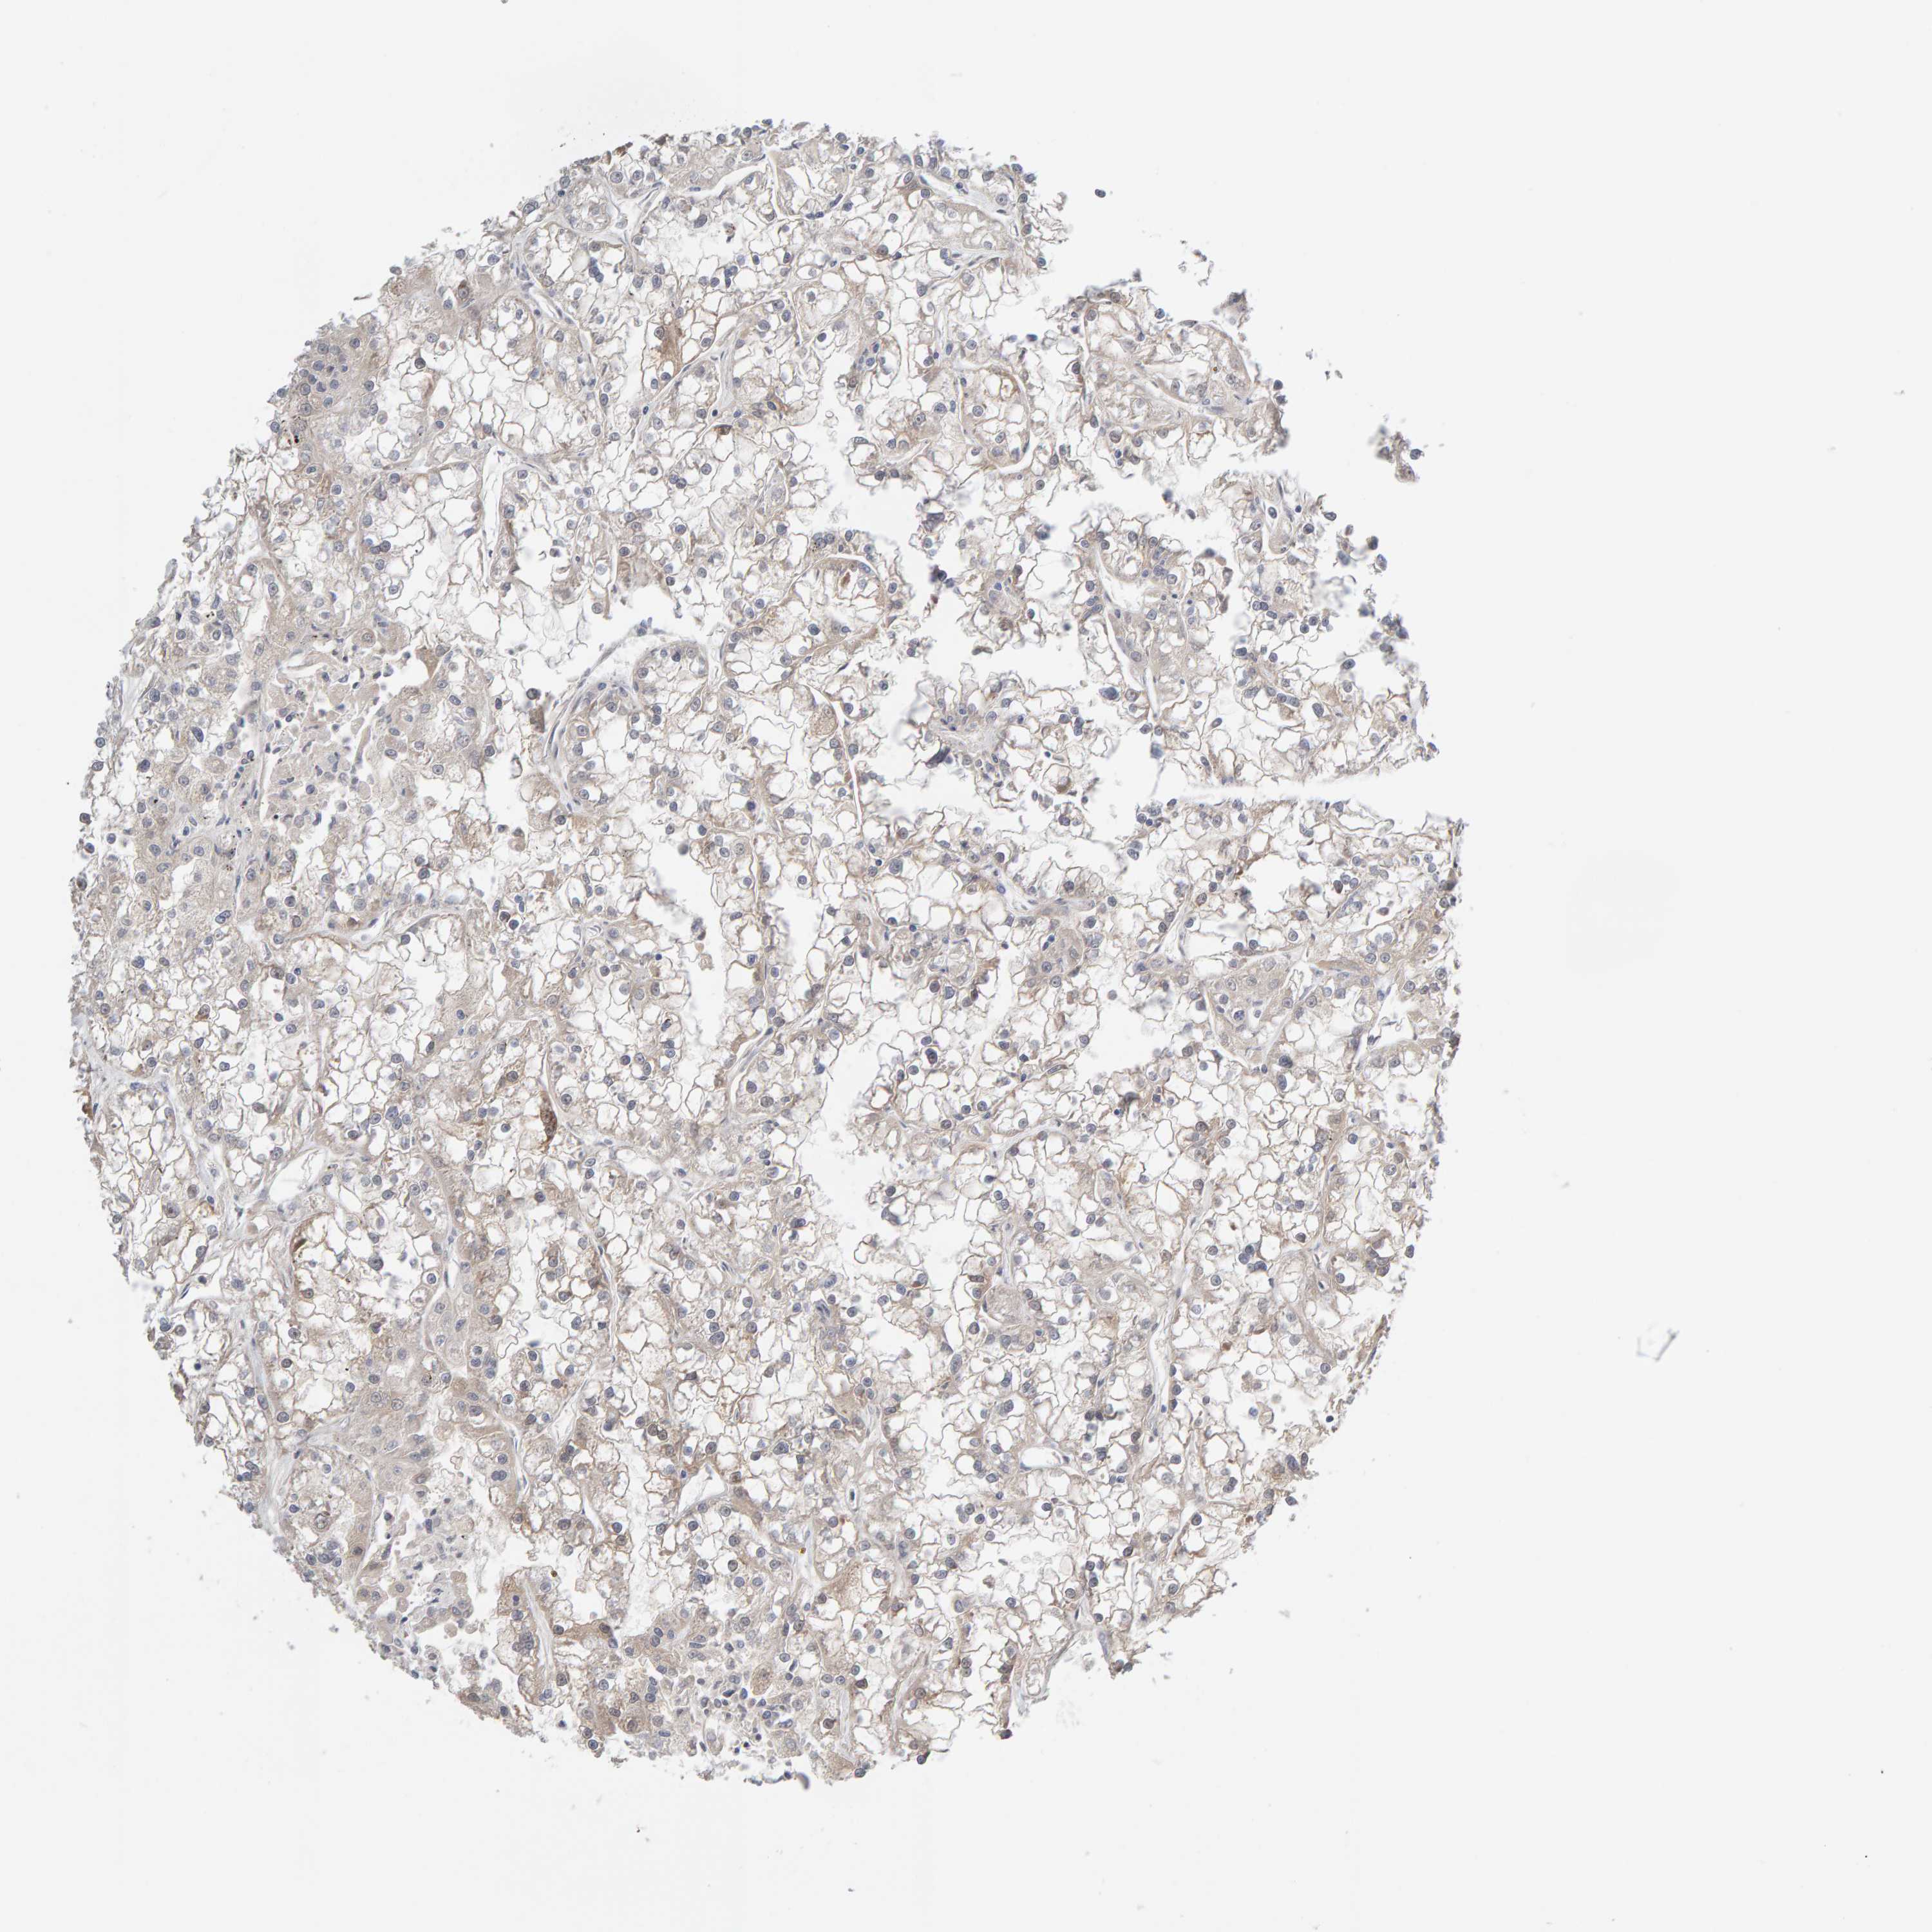

KIDNEY RENAL CLEAR CELL CARCINOMA (VALIDATION) - Interactive survival scatter ploti

The Survival Scatter plot shows the clinical status (i.e. dead or alive) for all individuals in the patient cohort, based on the same data that underlies the corresponding Kaplan-Meier plots. Patients that are alive at last time for follow-up are shown in blue and patients who have died during the study are shown in red.

The x-axis shows the expression levels (FPKM) of the investigated gene in the tumor tissue at the time of diagnosis. The y-axis shows the follow-up time after diagnosis (years). Both axes are complimented with kernel density curves demonstrating the data density over the axes. The top density plot shows the expression levels (FPKM) distribution among dead (red) and alive patients (blue). The right density plot shows the data density of the survived years of dead patients with high and low expression levels respectively, stratified using the cutoff indicated by the vertical dashed line through the Survival Scatter plot. This cutoff is automatically defined based on the FPKM cutoff that minimizes the p-score. The cutoff can be changed by dragging the vertical line or by entering a cutoff value in the square labeled "Current cut-off".

Under the Survival Scatter plot the p-score landscape (black curve; left axis) is shown together with dead median separation (red curve; right axis). Dead median separation is the difference in median mRNA expression between patients who have died with high and low expression, respectively. It is calculated as follows: median FPKM expression of dead patients with high expression - median FPKM expression of dead patients with low expression. This is intended to aid the user in visually exploring custom cutoffs and the associated p-scores and dead median separation.

Individual patient data is displayed and can be filtered by clicking on one or more of the category buttons on the top of the page. Categories describing expression level and patient information include: high, low, alive, dead, female, male and tumor stages. The scale of the x-axis can be toggled between linear and log-scale by clicking on the "x log" button. Mouse-over function shows TCGA ID, patient information and mRNA expression (FPKM) for each patient.

& Survival analysisi

Kaplan-Meier plots summarize results from analysis of correlation between mRNA expression level and patient survival. Patients were divided based on level of expression into one of the two groups "low" (under cut off) or "high" (over cut off). X-axis shows time for survival (years) and y-axis shows the probability of survival, where 1.0 corresponds to 100 percent.

GFUS is not prognostic in Kidney Renal Clear Cell Carcinoma (validation)

Best expression cut offi

Based on the FPKM value of each gene, patients were classified into two groups and association between prognosis (survival) and gene expression (FPKM) was examined. The best expression cut-off refers the FPKM value that yields maximal difference with regard to survival between the two groups at the lowest log-rank P-value. Best expression cut-off was selected based on survival analysis .

When clicking on this number, the vertical dashed line indicating cut-off, the interactive survival plot, and the Kaplan-Meier curve will be adjusted to show results based on the best expression cut-off.

: 29.22

Average pTPM 28.6

Number of samples 100